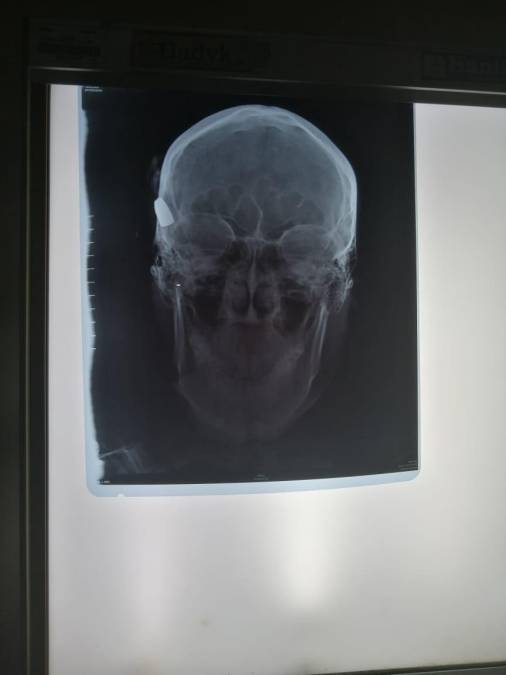

1 / 8Un niño de siete meses de nacido falleció luego de que una bala perdida le impactara en su cabeza.

2 / 8El menor fue identificado como Marvin Omar Ebanks Sevilla.

7 / 8En el fatal incidente también resultó herido el hermano de la víctima, identificado como Brayan David Ebanks (de 14 años).

8 / 8En el caso de Brayan, la misma bala impactó en su cabeza y se debate entre la vida y la muerte en el hospital Mario Catarino Rivas, de San Pedro Sula.